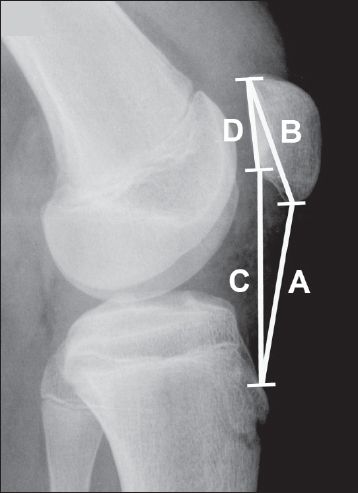

In cases of patella alta (when the patella is in a high position), there is reduced contact between the patella and trochlea during early knee flexion.(3,5,7) Using the Insall-Salvati method, patella alta is present when the length of the patellar tendon divided by the maximal diagonal length of the patella on a lateral knee radiograph produces a ratio of more than 1.2 (normal ratio: 1.0) (

Fig. 3

Lateral knee radiograph shows patella alta in a 14-year-old boy. The Insall-Salvati ratio, or the length of the patellar tendon (line A) divided by the maximal diagonal length of the patella (line B), is 1.4. In the modified Insall-Salvati method, the distance between the inferior articular surface of the patella and the patellar tendon insertion (line C) is divided by the length of the patellar articular surface (line D), giving a ratio of 2.4.